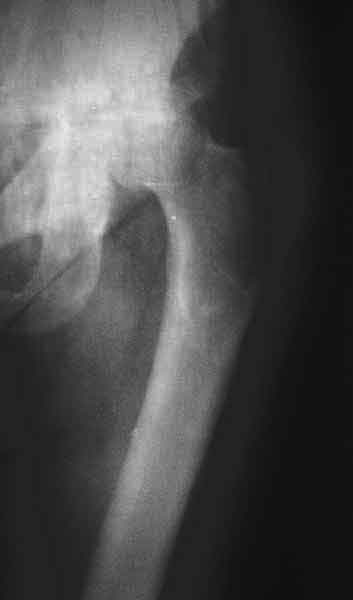

Еще пара фото, ситуация несколько иная, задачи те же, открытое вправление застарелого вывиха в 2002, молодой возраст. Сейчас госпитализирована для эндопротезирования.